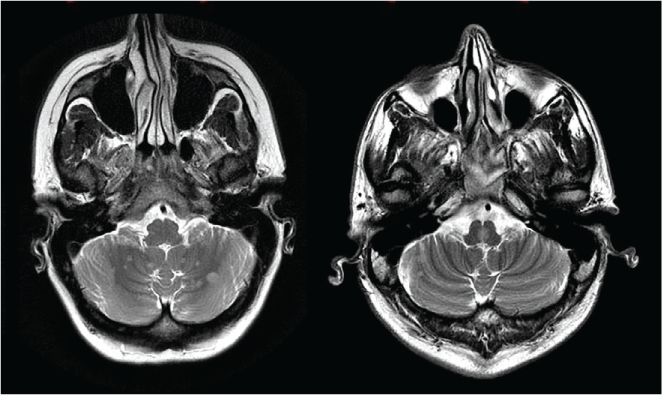

For MRI data, only brain scans obtained on the same 1.5-T clinical service MRI used for standard clinical care at the London MS Clinic were included. These clinical scans were completed as per full MS MRI protocol, with a slice thickness of 5 mm. T2-weighted axial images were examined and corroborated with fluid-attenuated inversion recovery images when in doubt about lesion presence. These data were collected by two authors (J.A.L. and S.M.) and reviewed/confirmed by a neuroradiologist with expertise in MS (M.S.) using picture archiving and communication system (Centricity; GE Healthcare, Milwaukee, WI) and free DICOM viewer (MicroDICOM) software. Both brainstem and cerebellar lesions were examined—specifically, the total number of posterior fossa lesions with an axial diameter of 2 mm or greater, as well as total lesions in the brainstem and cerebellum separately (Figure 1). The previously mentioned measures were selected based on previous MRI lesion analysis studies and the 2010 McDonald diagnostic criteria, which by convention uses 1.5-T scanner T2-weighted images to detect lesions in noncortical regions of the brain.2 18 19 These measures have been shown to have strong intrarater and interrater reliability.18

T2-weighted axial images demonstrate multiple hyperintense lesions in posterior fossa, seen in cerebellar hemispheres and in middle brainstem